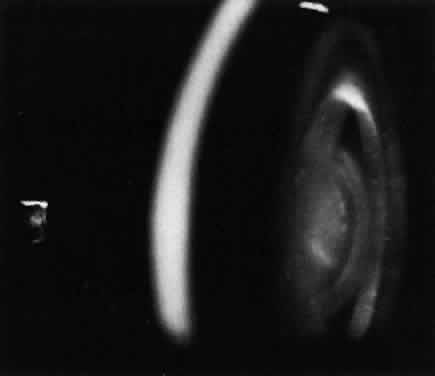

Progressive diffuse punctate stromal corneal opacities occur in all patients. They may conceal retinal degeneration and result in progressive visual loss.14,15 When the retina can be evaluated, a retinitis pigmentosa-like picture indistinguishable from other forms of heredofamilial retinal pigmentary dystrophies usually is present. The electroretinogram is diminished or nonrecordable.16 Glaucoma is relatively rare17 but has been reported in some patients.14,18 Optic nerve head swelling and optic atrophy are common10 (Fig. 2). Congenital cataracts occasionally have been observed.19

Fig. 2. Optic nerve head and peripapillary elevation in a patient with Hurler syndrome (MPS I-H).